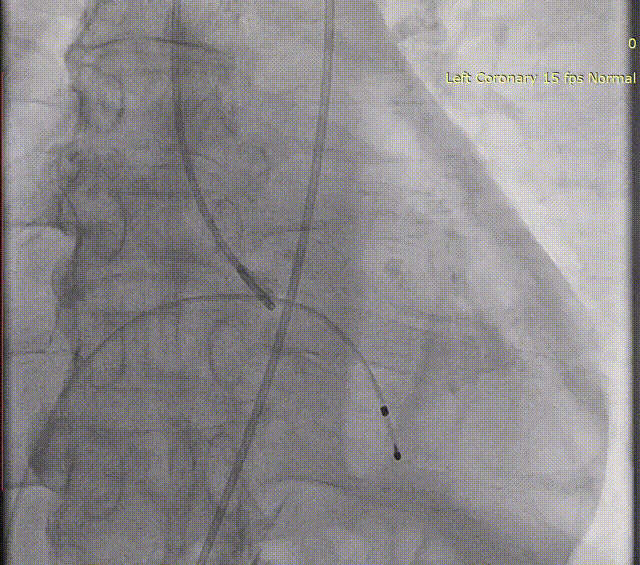

主动脉根部造影

肝位左心耳造影

测量左心耳开口24.9mm,深度22mm